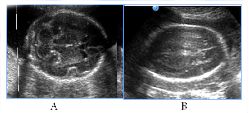

In 5fetuses with severe prolonged course of placental dysfunction we antenatally detected modified insular complex with anomalously broad lateral (Sylvian) sulcus as a signs of abnormal gyration and sulcation (Figure 7). US images of cortical dysplasia in our study were associated with fetal intrauterine growth retardation (IGR), Oligohydramnios, metabolic acidosis and neuro infection. These fetuses had adverse GPO (3cases) and extremely unfavorable CPO (2cases) (Figure 8).

Figure 7NSG of two fetuses of the same gestational age (29 GW) with normal brain image (A), also with a signs of cortical dysplasia (B).

Figure 8Abnormal image of the cerebral cortex as a manifestation of abnormal neuronal migration in two fetuses in 3rd trimester of pregnancy, fetal US and neonatal MRI.

NSG of two fetuses of the same gestational age (29 GW) with normal brain image (A), also with a signs of cortical dysplasia (B).

Figure 8 Abnormal image of the cerebral cortex as a manifestation of abnormal neuronal migration in two fetuses in 3rd trimester of pregnancy, fetal US and neonatal MRI. A, B) 30GW, cortical dysplasia, the type of neuronal heterotopia and pachygyria, long-term violations as severe epilepsy and retardation of development in catamnesis. C,D,E) 29 GW, cortical dysplasia in the fetus with significant IGR and antenatal distress, postnatal transmantian dysplasia, lissencephaly and presilvian polymicrogyria that clinically was accompanied by hypotension and child neurological disabilities.